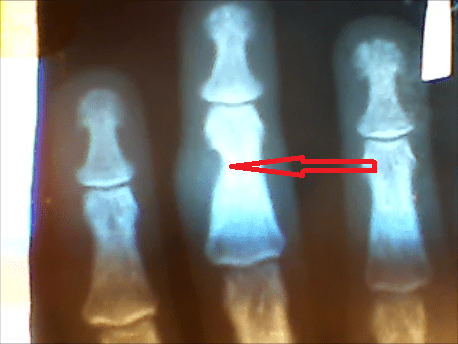

Еще в 2005 году я стал замечать, что у меня на второй фаланге среднего пальца левой руки появилась какая-то ямка и как будто-бы в кости и эта «бяка» стала временами беспокоить, особенно при физических нагрузках ( и по закону бутерброда как правило по ночам). Во время очередного годового медосмотра(кто служил знает его заставляют проходить всех) я обратил внимание на это хирурга (еще один совет, не бойтесь во время таких осмотров обращать внимание специалистов на свои проблемы — помните «спасение утопающих дело рук самих утопающих»). Он послал меня на рентген см. снимок № 1. То что я там увидел меня очень расстроило, а еще больше расстроил комментарий хирурга. Он заявил что такое заболевание практически не излечимо и меня ожидает ампутация фаланги, если я раньше её не сломаю. Меня такой поворот событий конечно же не устраивал.

Кто читал мои предыдущие статьи помнит, для остальных напомню. Как раз в это время я активно принимал перекись водорода( как читайте в этом же блоге мою статью о лечении перекисью сахарного диабета). Помимо этого я начал делать компрессы на больной палец с гидроперитом(это та же перекись только в таблетках). Для приготовления компресса я в 0.5 стакана теплой воды растворял 10 таблеток гидроперита и делал компресс на область больной фаланги ( более подробно как и сколько делать компрессов читайте в этом же блоге мою статью о лечении перекисью щитовидной железы — не хочу повторяться).

После двух курсов боли прекратились и я потихоньку стал забывать про эту болячку. Я вспомнил о ней только в 2010 году, когда проходил ВВК при увольнении по болезни(нет болей не было просто решил заодно проверить). Какова же была моя радость и удивление врачей когда я и они сравнили два снимка №1 и №2. Хирург не поверил и назначил повторный снимок, но он полностью подтвердил ремиссию костной ткани. Они стали меня допытывать чем и как я лечился(ведь всё это происходило на фоне сахарного диабета, при котором как всем известно даже раны плохо заживают, а тут полная ремиссия ). Я им рассказал про перекись водорода про методику профессора И.П. Неумывайкина по которой я лечился и лечусь до сих пор(дай бог ему здоровья, если он ещё жив, я слышал у него последнее время были большие проблемы со здоровьем).